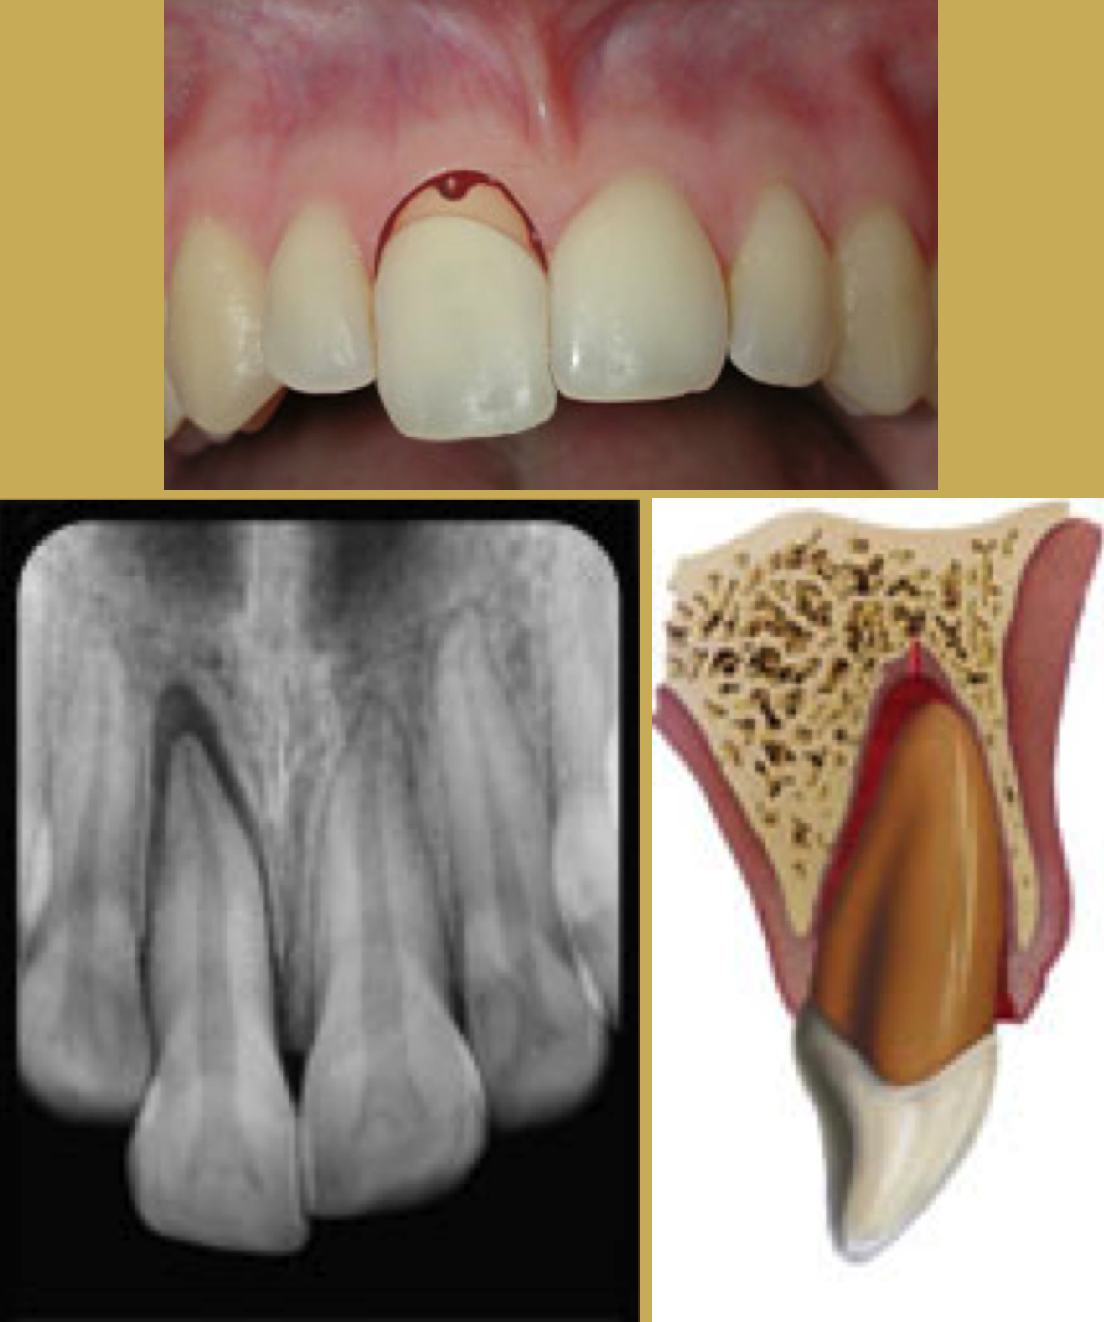

Tooth Intrusion

Tooth intrusion occurs when the tooth has been driven into the alveolar process due to an axially directed impact (Figure 3). This is the most severe form of displacement injury. Athletes with intrusively luxated teeth should be immediately removed from play and transported to a sports emergency dentist.44

Pulpal necrosis occurs in 96% of intrusive displacements and is more likely to occur in teeth with fully formed roots. Immature root development will usually mean spontaneous re-eruption. Mature root development will require repositioning, surgery, and splinting or orthodontic extrusion. Treat relatively quickly since the pulp usually becomes necrotic - this can be treated with temporary filling of calcium hydroxide paste followed by root canal therapy.

Fig 3. Images of Intrusion

Figure 3